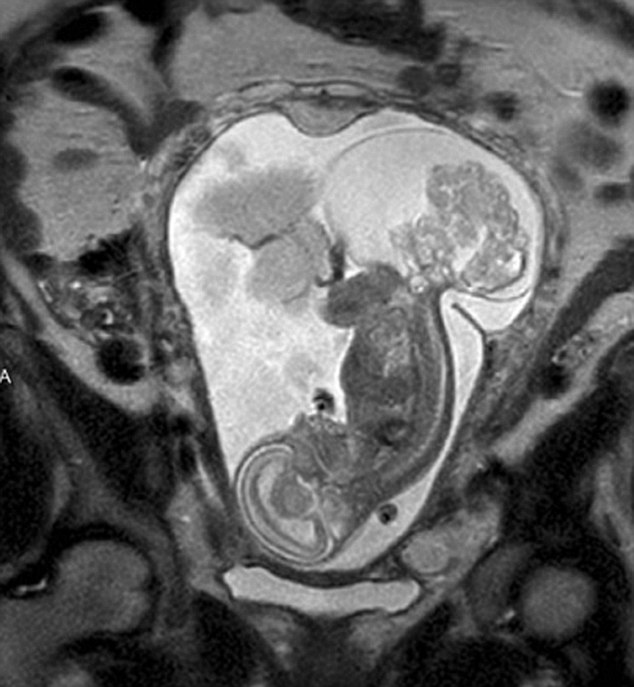

【环球网综合报道】据英国《每日邮报》10月23日报道,美国得克萨斯州布兰诺市的女子玛格丽特·伯默(Margaret Boemer)怀孕16周时去做产检,不幸被告知胎儿尾骨上长有肿瘤,她与医生商量后决定先将胎儿取出进行肿瘤切除手术,再将其送回子宫继续孕育。最终手术圆满成功,12周后胎儿足月出生。

玛格丽特称自己当时听到产检结果时十分害怕。“医生说宝宝长了骶尾部畸胎瘤。我们很震惊,很害怕,因为我们根本不知道这个什么瘤到底意味着什么。”随着时间流逝,肿瘤越来越大,胎儿满23周时肿瘤已危及其性命。医生告诉玛格丽特,若想胎儿存活,只能将胎儿取出进行手术,然后再放回子宫,否则只能立即终止孕期。“这很容易做决定:让肿瘤夺去孩子性命,或是给孩子存活的机会。我们当然选择后者。”玛格丽特说。

医生将胎儿取出20分钟后,便放回母体子宫。12周后,宝宝足月出生。玛格丽特称:“这可以说是她的第二次出生了。只要她有机会活下来,我愿意承受所有风险。”(实习编译:高睿 审稿:朱盈库)